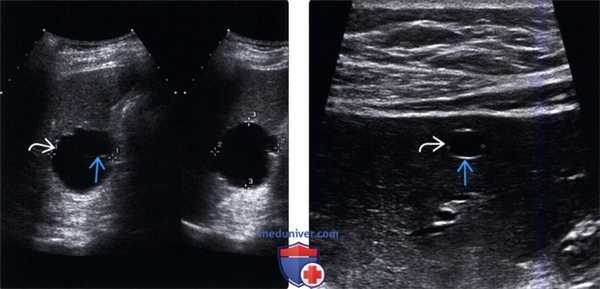

• Кисты ворот печени (перибилиарные кисты):

о Четко отграниченные кистозные образования круглой/овальной/трубчатой формы вдоль портальных триад

о Обычно множественные: сливные или дискретно расположенные очаги

о Тонкие и гладкие стенки без видимых включений

о Размер варьирует от 2 мм до 2 см

о Не сообщается с желчевыводящей системой

о Кистозные образования с четкими границами круглой/овальной/трубчатой формы, расположенные вдоль портальных триад

о Обычно множественные: дискретное или конфлюэнтное расположение

о Гладкие и тонкие стенки без внутристеночных образований

о Размеры варьируют от 2 мм до 2 см

о Отсутствует связь с желчевыводящей системой

(Правый) При поперечном трансабдоминальном ультразвуковом сканировании в левой доле печени визуализируется эхинококковая киста, содержащая множественные дочерние кисты на периферии, содержимое в центре неоднородное. Также наблюдается ассоциированное заднее акустическое усиление. (Левый) При цветовой допплерографии визуализируются перибилиарные кисты, прилежащие к воротной вене. Перибилиарные кисты не следует путать с расширенными желчными протоками, которые имеют более трубчатый и вытянутый вид.